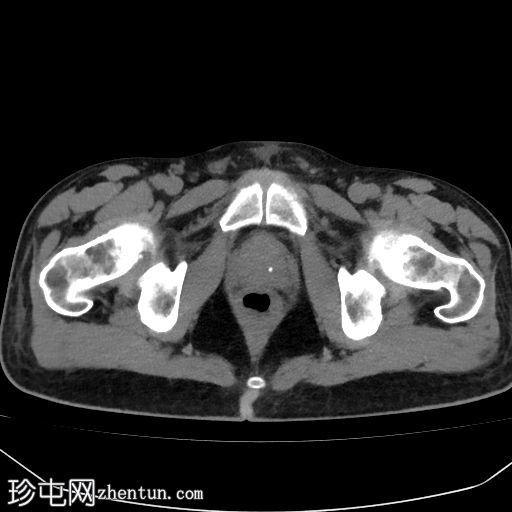

4l.jpg

轴位增强扫描

延迟期

在多期CT或MRI扫描中,这些浸润性结节表现出明显的非环状动脉期高强化(APHE),这是诊断的关键特征。然而,随后的“消退”通常不明显,且由于肝硬化肝脏背景强化不均匀,其解读较为复杂。